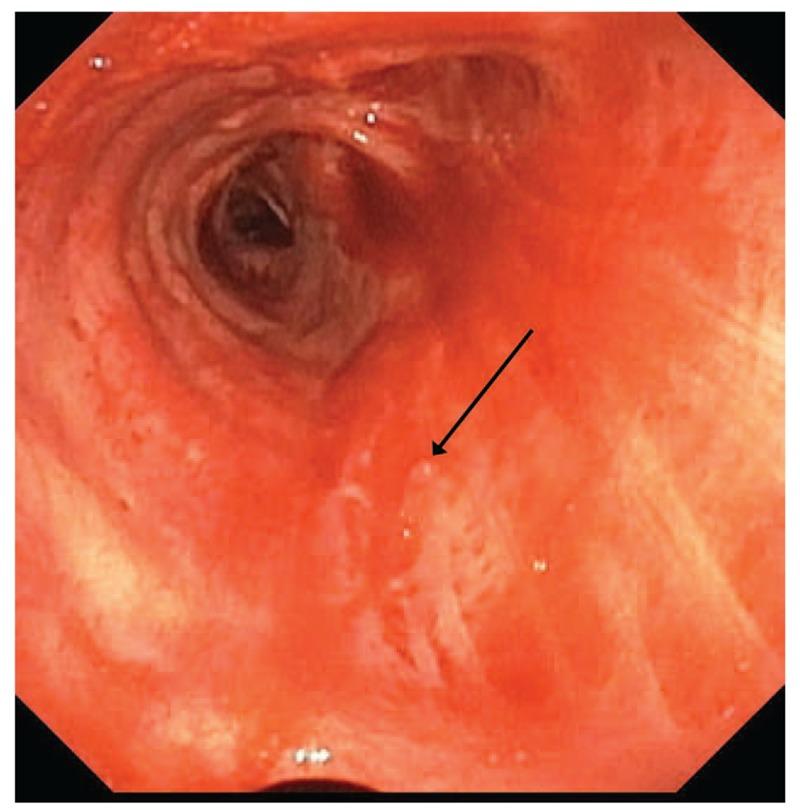

Dieulafoy lesions are aberrantly large submucosal arteries most frequently associated with gastrointestinal hemorrhage. They are rarely identified in the bronchial submucosa and can cause massive hemoptysis.

All episodes were due to Dieulafoy lesions of the bronchus based on bronchoscopic appearance.

Dieulafoy病变是异常粗大的黏膜下动脉,最常与胃肠道出血相关。它们在支气管黏膜下很少见,可导致大量咯血。

根据支气管镜检查表现,所有发作均归因于支气管的Dieulafoy病变。